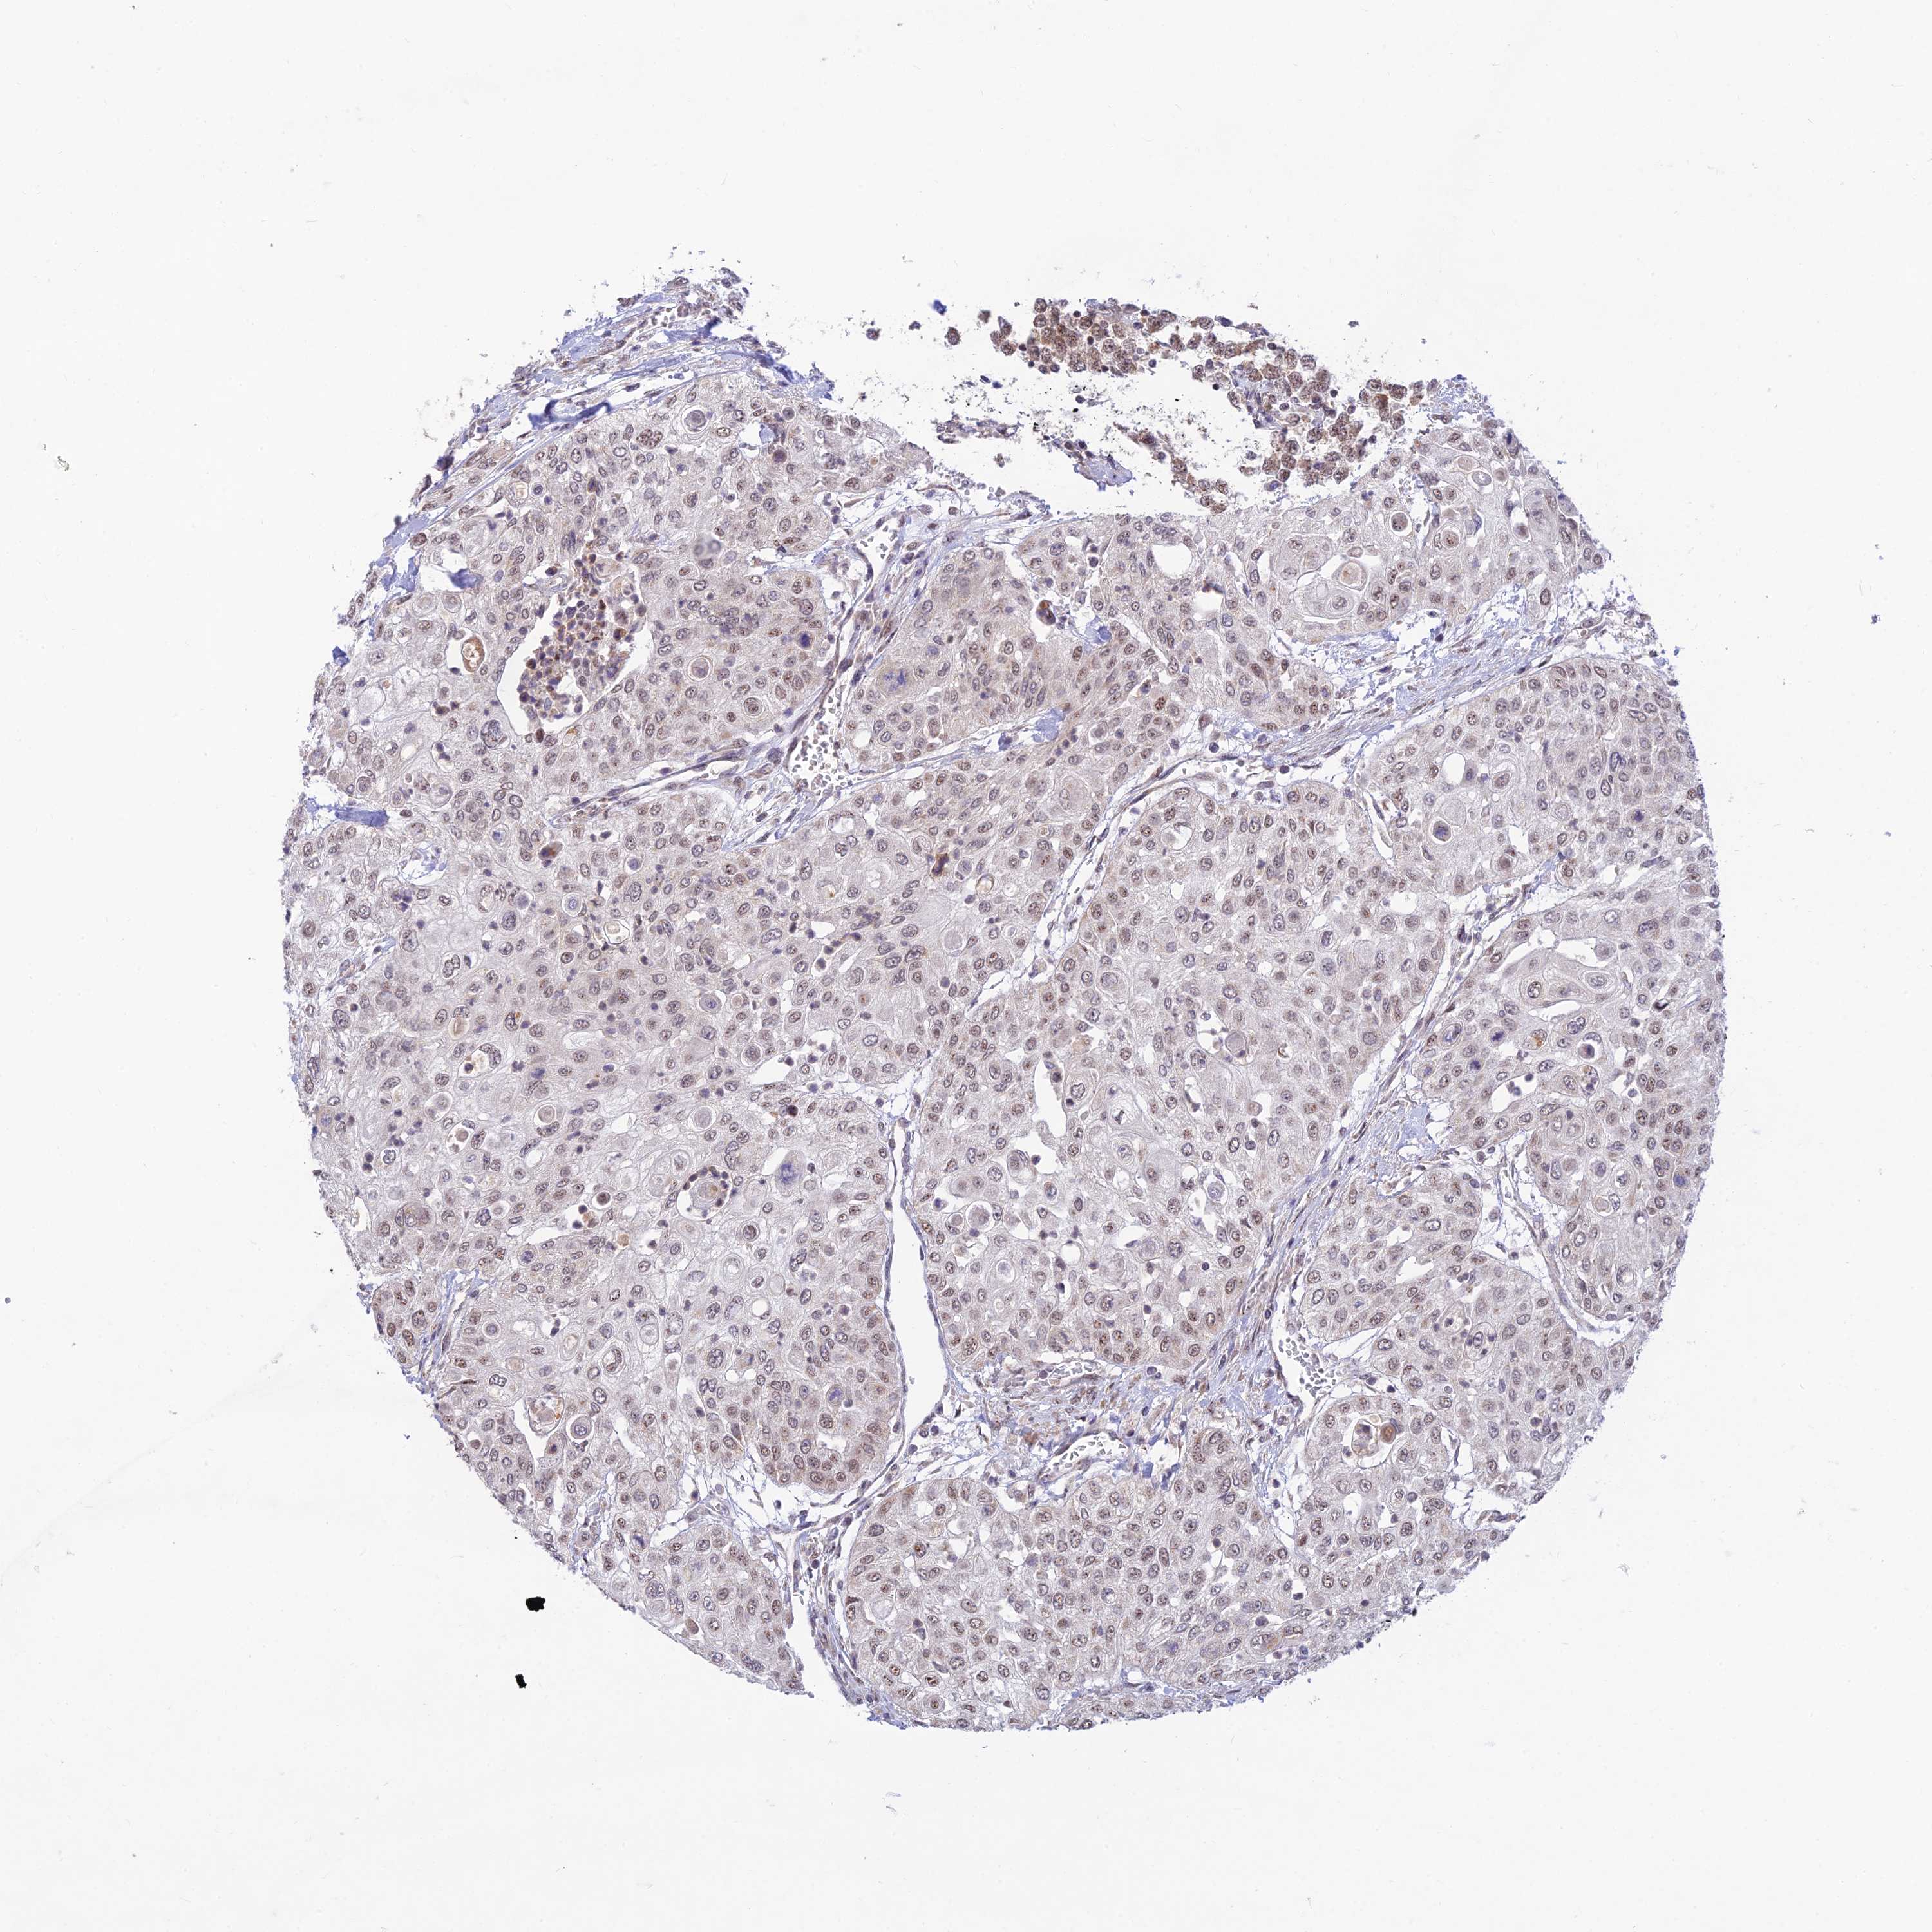

UROTHELIAL CANCER - Protein expressioni

A mouse-over function shows sample information and annotation data. Click on an image to view it in a full screen mode. Samples can be filtered based on level of antibody staining by selecting one or several of the following categories: high, medium, low and not detected. The assay and annotation is described here.

Note that samples used for immunohistochemistry by the Human Protein Atlas do not correspond to samples in the TCGA dataset.

Antibody stainingi

Antibody staining in the annotated cell types in the current human tissue is reported as not detected, low, medium, or high, based on conventional immunohistochemistry profiling in selected tissues. This score is based on the combination of the staining intensity and fraction of stained cells.

Each image is clickable and will lead to virtual microscopy that enables deeper exploration of all samples and also displays staining intensity scores, fraction scores and subcellular localization as well as patient and tissue information for each sample.

Antibody HPA042672

Staining

High

Medium

Low

Not detected

Intensity

Strong

Moderate

Weak

Negative

Quantity

>75%

75%-25%

<25%

None

Location

Nuclear

Cytoplasmic/membranous

Cytoplasmic/membranous,nuclear

Urothelial carcinoma, High grade

Urothelial carcinoma, Low grade